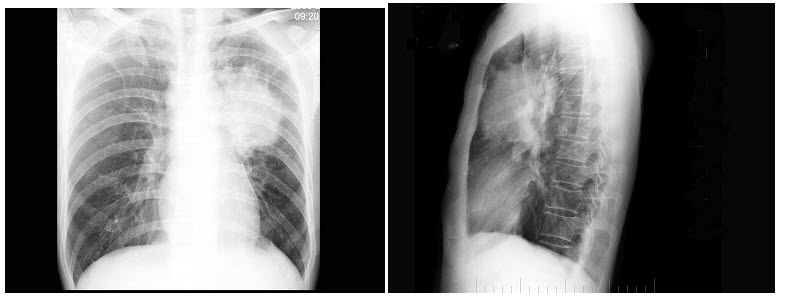

9、单项选择题

男,28岁,轻咳2个月,有盗汗。胸片如图